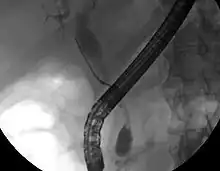

Imaging of the biliary tree

While abdominal imaging can be useful in the diagnosis of cholangiocarcinoma, direct imaging of the bile ducts is often necessary. Endoscopic retrograde cholangiopancreatography (ERCP), an endoscopic procedure performed by a gastroenterologist or specially trained surgeon, has been widely used for this purpose. Although ERCP is an invasive procedure with attendant risks, its advantages include the ability to obtain biopsies and to place stents or perform other interventions to relieve biliary obstruction.[12] Endoscopic ultrasound can also be performed at the time of ERCP and may increase the accuracy of the biopsy and yield information on lymph node invasion and operability.[55] As an alternative to ERCP, percutaneous transhepatic cholangiography (PTC) may be utilized. Magnetic resonance cholangiopancreatography (MRCP) is a non-invasive alternative to ERCP.[56][57][58] Some authors have suggested that MRCP should supplant ERCP in the diagnosis of biliary cancers, as it may more accurately define the tumor and avoids the risks of ERCP.[59][60][61]